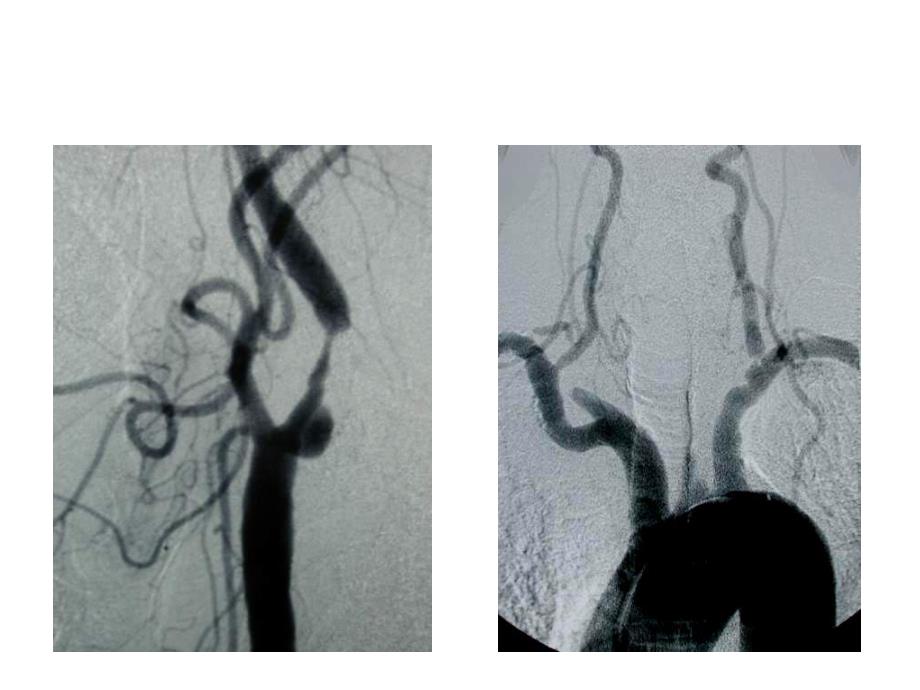

2、演变:历史演变:1980年年,Kerber等人首先应用腔内球囊扩张术治疗颈动脉狭窄等人首先应用腔内球囊扩张术治疗颈动脉狭窄.为增强疗效为增强疗效 及减少术后再狭窄及减少术后再狭窄,又采用了支架植入又采用了支架植入.1989 年德国多特蒙德介入科医生年德国多特蒙德介入科医生Klaus Mathias开始首例开始首例CAS.发展现状:广泛接受,迅速发展发展现状:广泛接受,迅速发展颈动脉狭窄 支架置入术支架置入前后的比较支架+保护伞支架置入+保护伞n“右侧颈动脉支架远端高度狭窄,左侧颈动脉支架闭塞”支架置入术后并发症支架置入术后并发症典型病例典型病例颈总动脉端颈总动脉端颈内动脉端颈内动脉端颈总动脉端

3、颈总动脉端颈内动脉端颈内动脉端颈内动脉和支架一起取出颈内动脉和支架一起取出治疗过程治疗过程取出的支架和颈内动脉取出的支架和颈内动脉颈总动脉端颈总动脉端颈内动脉端颈内动脉端治疗过程治疗过程6mm PTFE 人造血管间置人造血管间置治疗结果治疗结果6mm PTFE 人造血管间置术后人造血管间置术后CTA治疗结果治疗结果6mm PTFE 人造血管间置术后人造血管间置术后CTACAS 中远期的严重并发症中远期的严重并发症 再狭窄再狭窄支架内再狭窄支架内再狭窄支架远端再狭窄支架远端再狭窄CAS 中远期中远期的严重并发的严重并发症症 再狭窄再狭窄严重严重(80%(80%以上以上)的再狭窄的再狭窄3%-28%3%-28%颈动脉内末剥脱术的疗效 1993-2003年间,30个国家126家医院的3120名病人随机接受了CEA或药物治疗(包括抗高血压药、抗凝药和降脂药),然后前瞻性随访5年,平均随访3.4年。手术30天内发生中风或死亡的危险为3.1%;对小于75岁的手术病人,5年中风危险为6.4%;而药物治疗是11.8%。这充分说明了颈动脉内膜切除术虽然存在一定的风险,但是在预防中风的发生上具有明显的疗效。